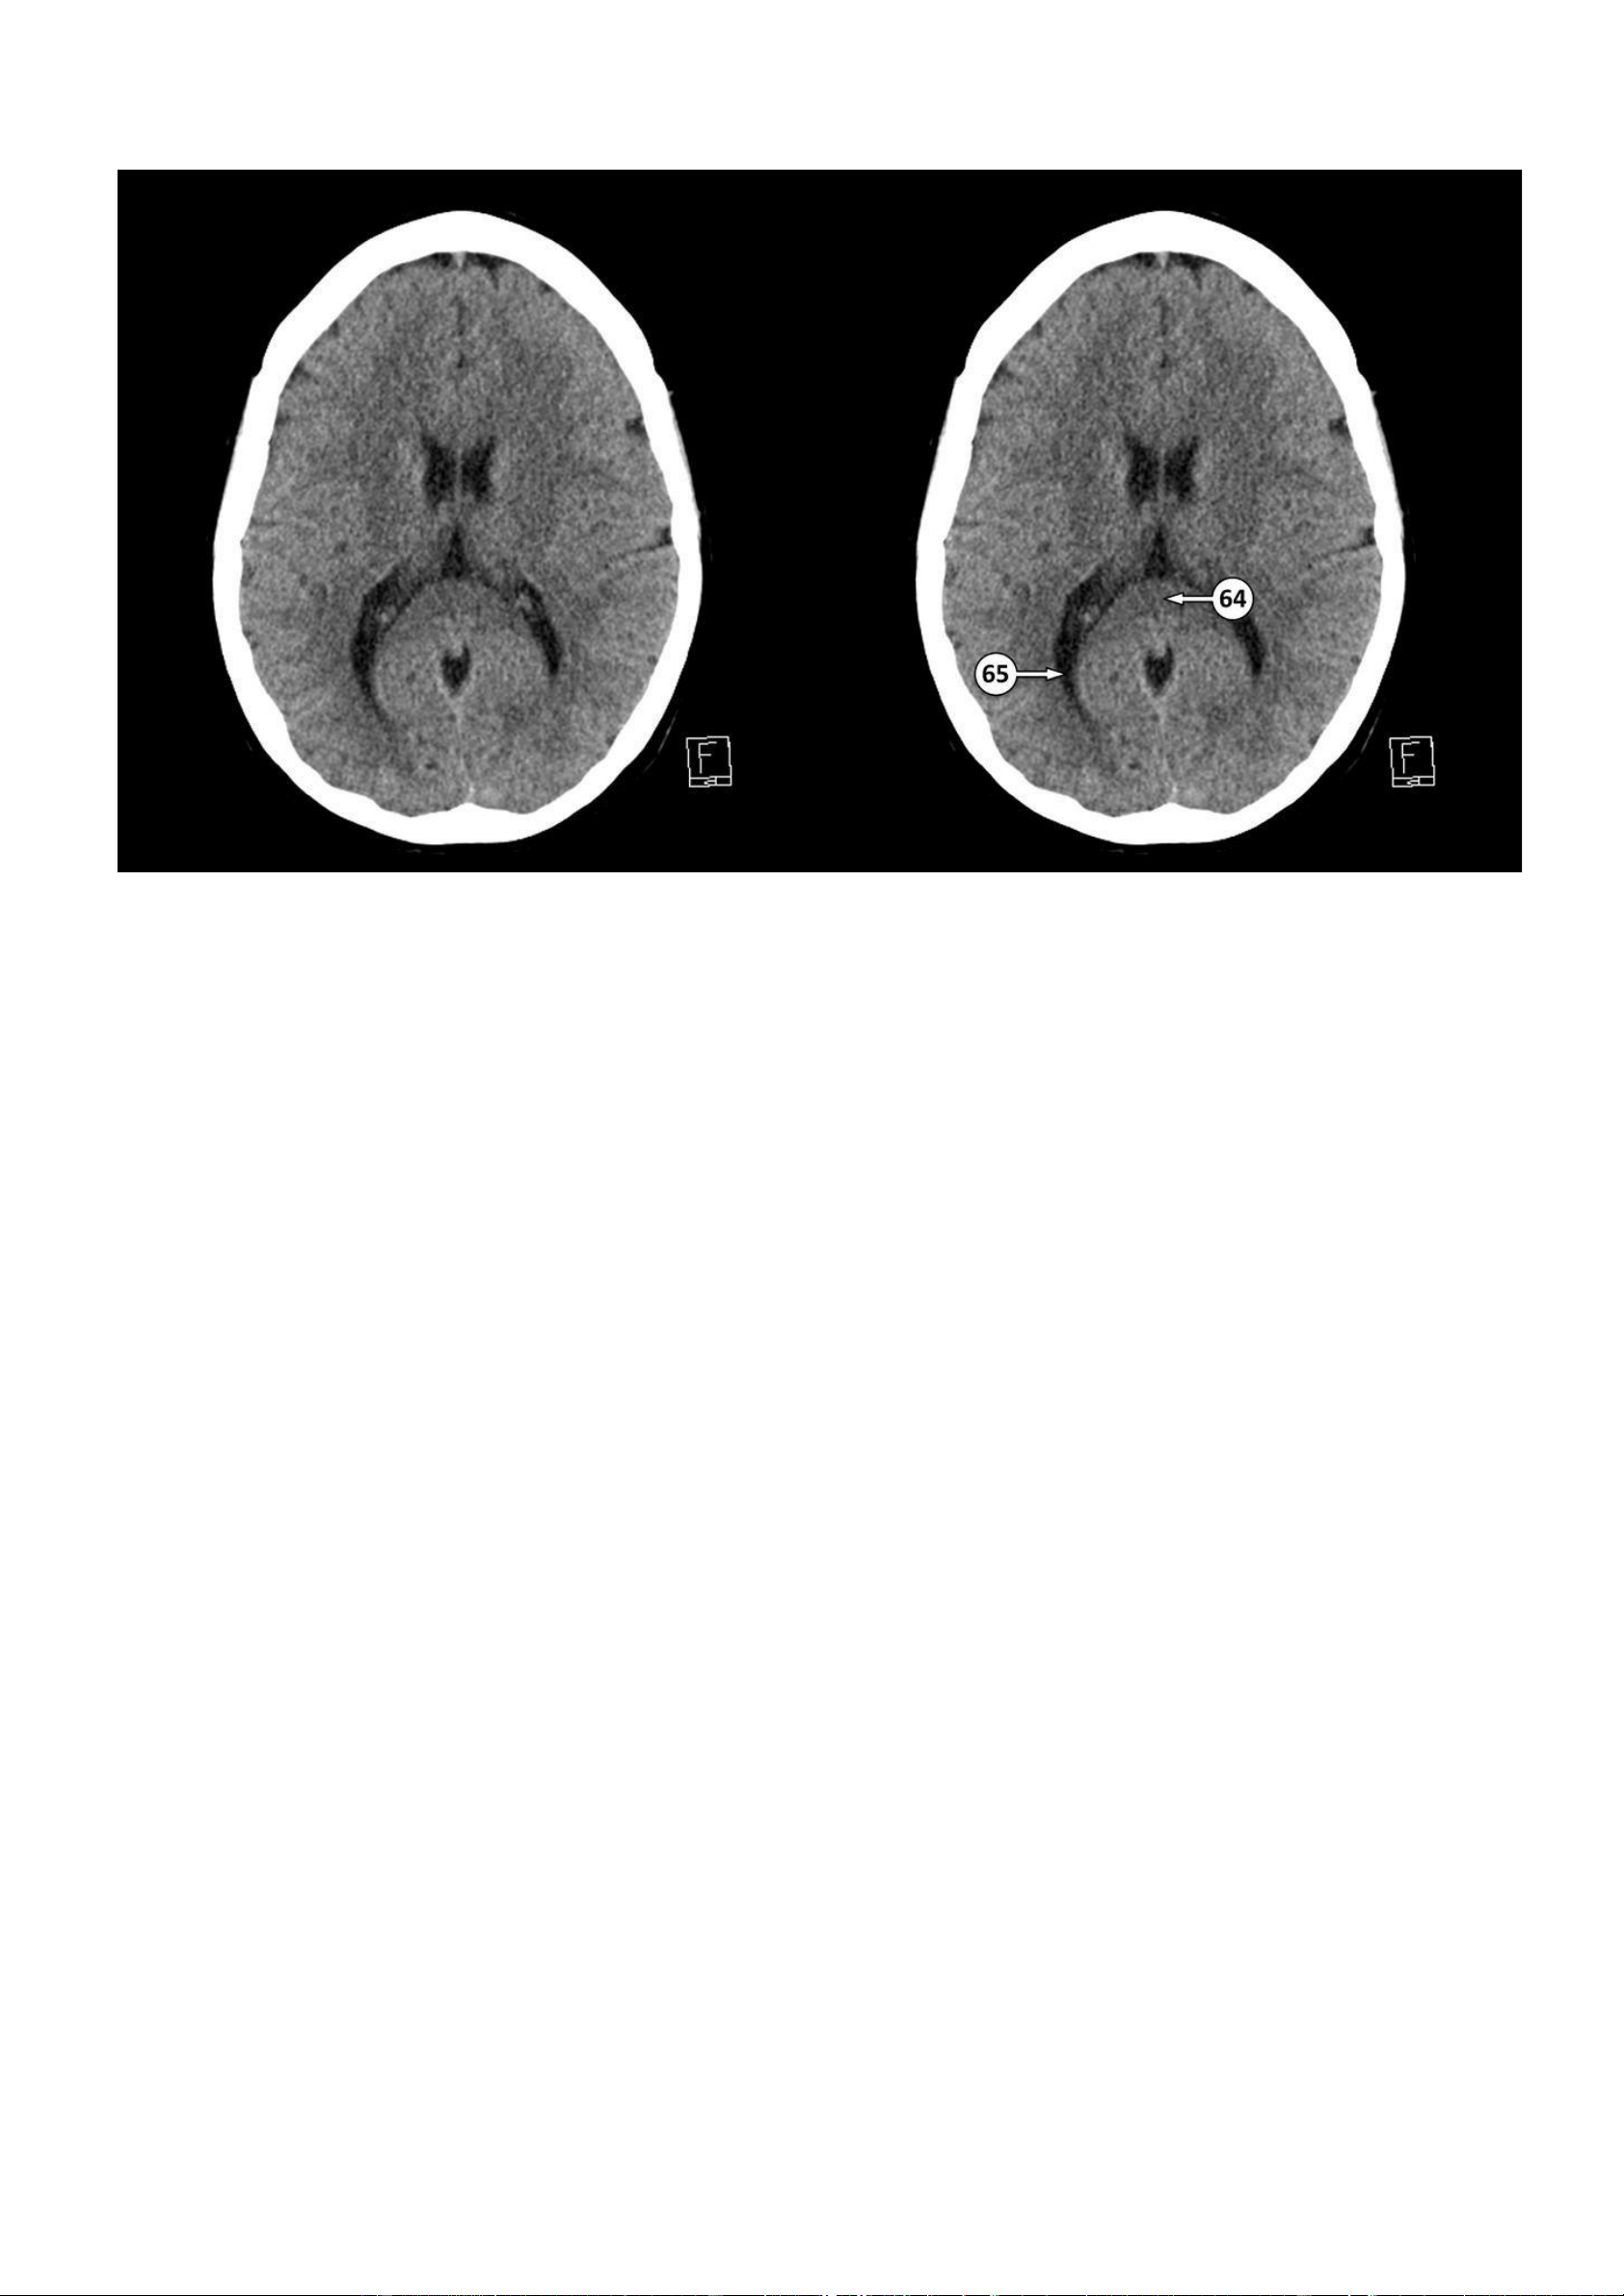

Thảo Thảo & Bé Nghìn Dặm 64: Lồi của thể chai

65: Sừng chẩm của não thất bên lOMoAR cPSD| 22014077